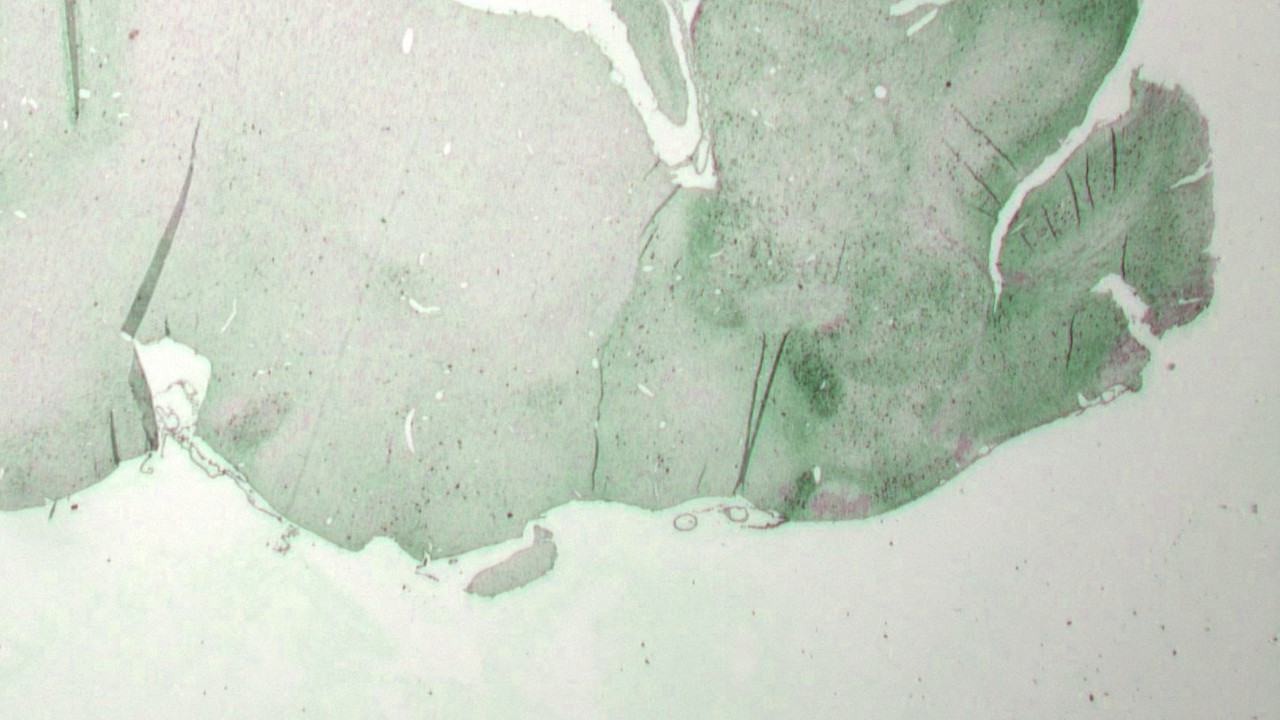

Investigación en animales para un medicamento seguro y eficaz

Las autoridades obligan a Lundbeck a llevar a cabo estudios en animales para avanzar en el desarrollo de medicamentos seguros y eficaces para tratar enfermedades mentales. Sólo llevaremos a cabo estudios con animales cuando no existan alternativas y cuando los beneficios superen los posibles riesgos para los animales. Proporcionamos el cuidado necesario a nuestros animales de experimentación y siempre trabajamos para mejorar nuestra política de investigación con animales, procedimientos e instalaciones para éstos.